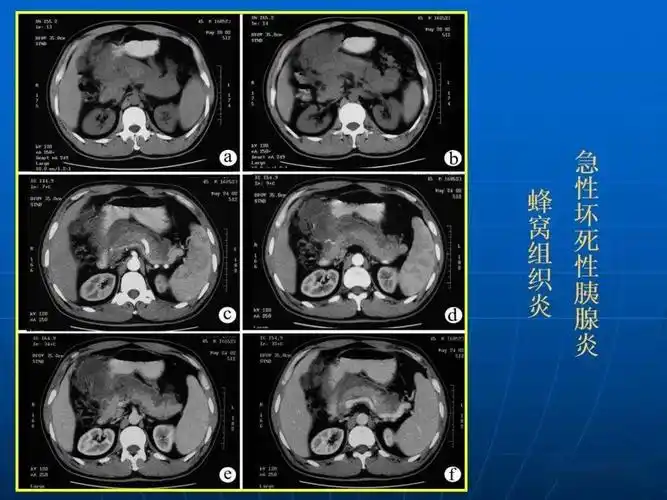

9种胰腺常见疾病的ct诊断